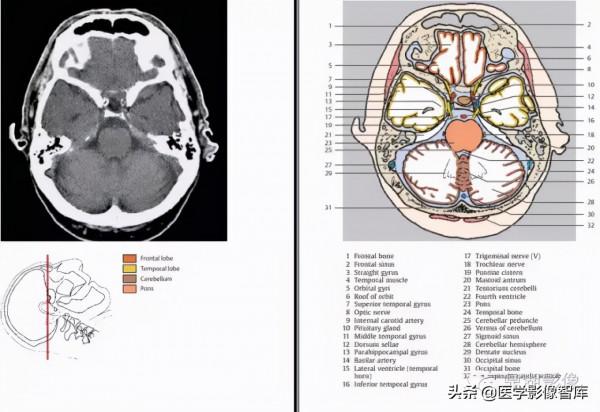

1.額竇 2.額骨 3.大腦鐮 4.眶回 5.直回 6.大腦前動脈 7.前交通動脈 8.頸內動脈 9.顳上回 10.顳中回 11.大腦中動脈 12.後交通動脈 13.視交叉 14.杏仁核 15.垂體 16.側腦室(顳角)17.鞍背 18.海馬 19.基底池?20.顳下回 21.大腦後動脈22.海馬旁回 23.小腦幕 24.基底動脈和基地溝 25.橋腦 26.乙狀竇 27.小腦角(中部)28.第四腦室 29.齒狀核 30.小腦蚓(上部)31.顳骨 32.竇匯 33.小腦半球 34.橫竇 35.枕骨

1.額骨 2.額竇 3.直回 4.顳肌 5.眶回 6.眶頂 7.顳上回 8.視神經 9.頸內動脈 10.垂體 11.顳中回 12.鞍背13.海馬旁回 14.基底動脈 15.側腦室(顳角) 16.顳下回 17.三叉神經 18.滑車神經 19.腦橋池 20.乳突竇21.小腦幕 22.第四腦室 23.橋腦 24.顳骨 25.小腦腳 26.小腦蚓 27.乙狀竇 28.小腦半球 29.齒狀核 30.枕竇 31.枕骨 32頭半棘肌